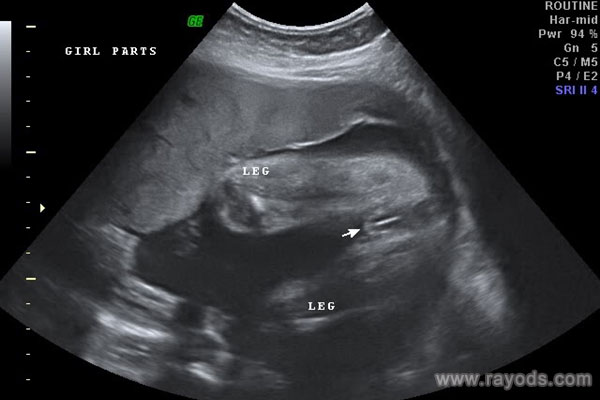

五个月女宝宝清晰b超图

上面分享的这张b超图就是典型的女宝宝b超图,一般五个月的时候,也就是怀孕20周之后,女宝宝的生殖器官甚至都可以清晰可见,完全可以凭肉眼就分辨得出,也可以看这张b超图中双腿间的性别特征。就对于这个b超角度,采取的是从屁股下面照上去的,其清晰程度取决于仪器,其次就是b超师的手法。

大家可以看到图中女宝的生殖器结构,上面有类似于线条的一杠,这就是女宝胎儿的外生殖器结构了,也就是我们所说的大小***,有的时候b超看到是一条线,大多时候是三条,有这一点,女宝就更好确认了。孕周大了之后,这个时候性别特征不仅很明显,而且非常清晰好分辨,看男女基本都是十有八九的事情。